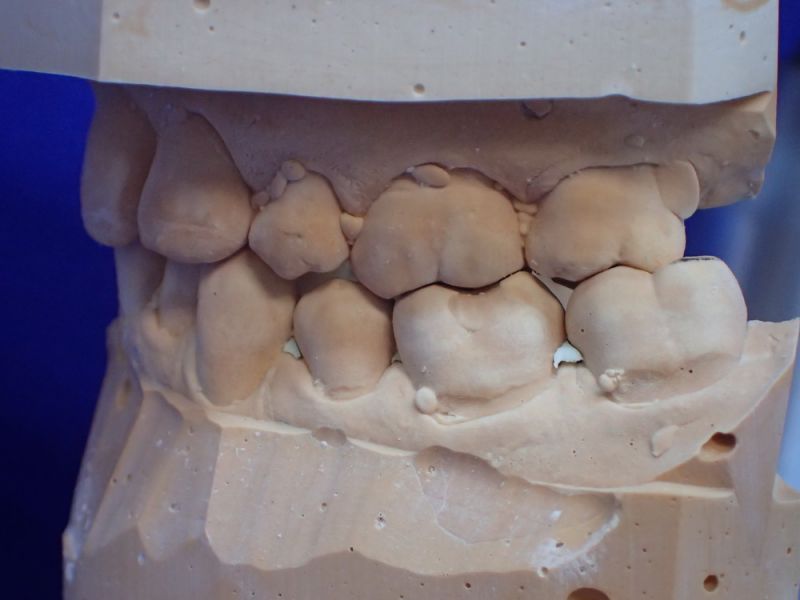

Patientin von der dänischen Grenze erhält einen adjustierten Aufbissbehelf

Obwohl die Patientin erkennbar eine gute Mundhygiene beteibt, zeigt sich im gesamten Oberkiefer und hier vor allem im Bereich der Backenzähne ein ausgeprägte und altersuntypisch weit voran geschrittener Knochenabbau.

Das Typische an diesen Zuständen besteht darin, dass der Knochen im Unterkiefer weitgehend normal erscheint, was bene gerade dafür spricht, dass es sich um kein mundhygienebedingtes Problem des Kieferknochenabbaus handelt.